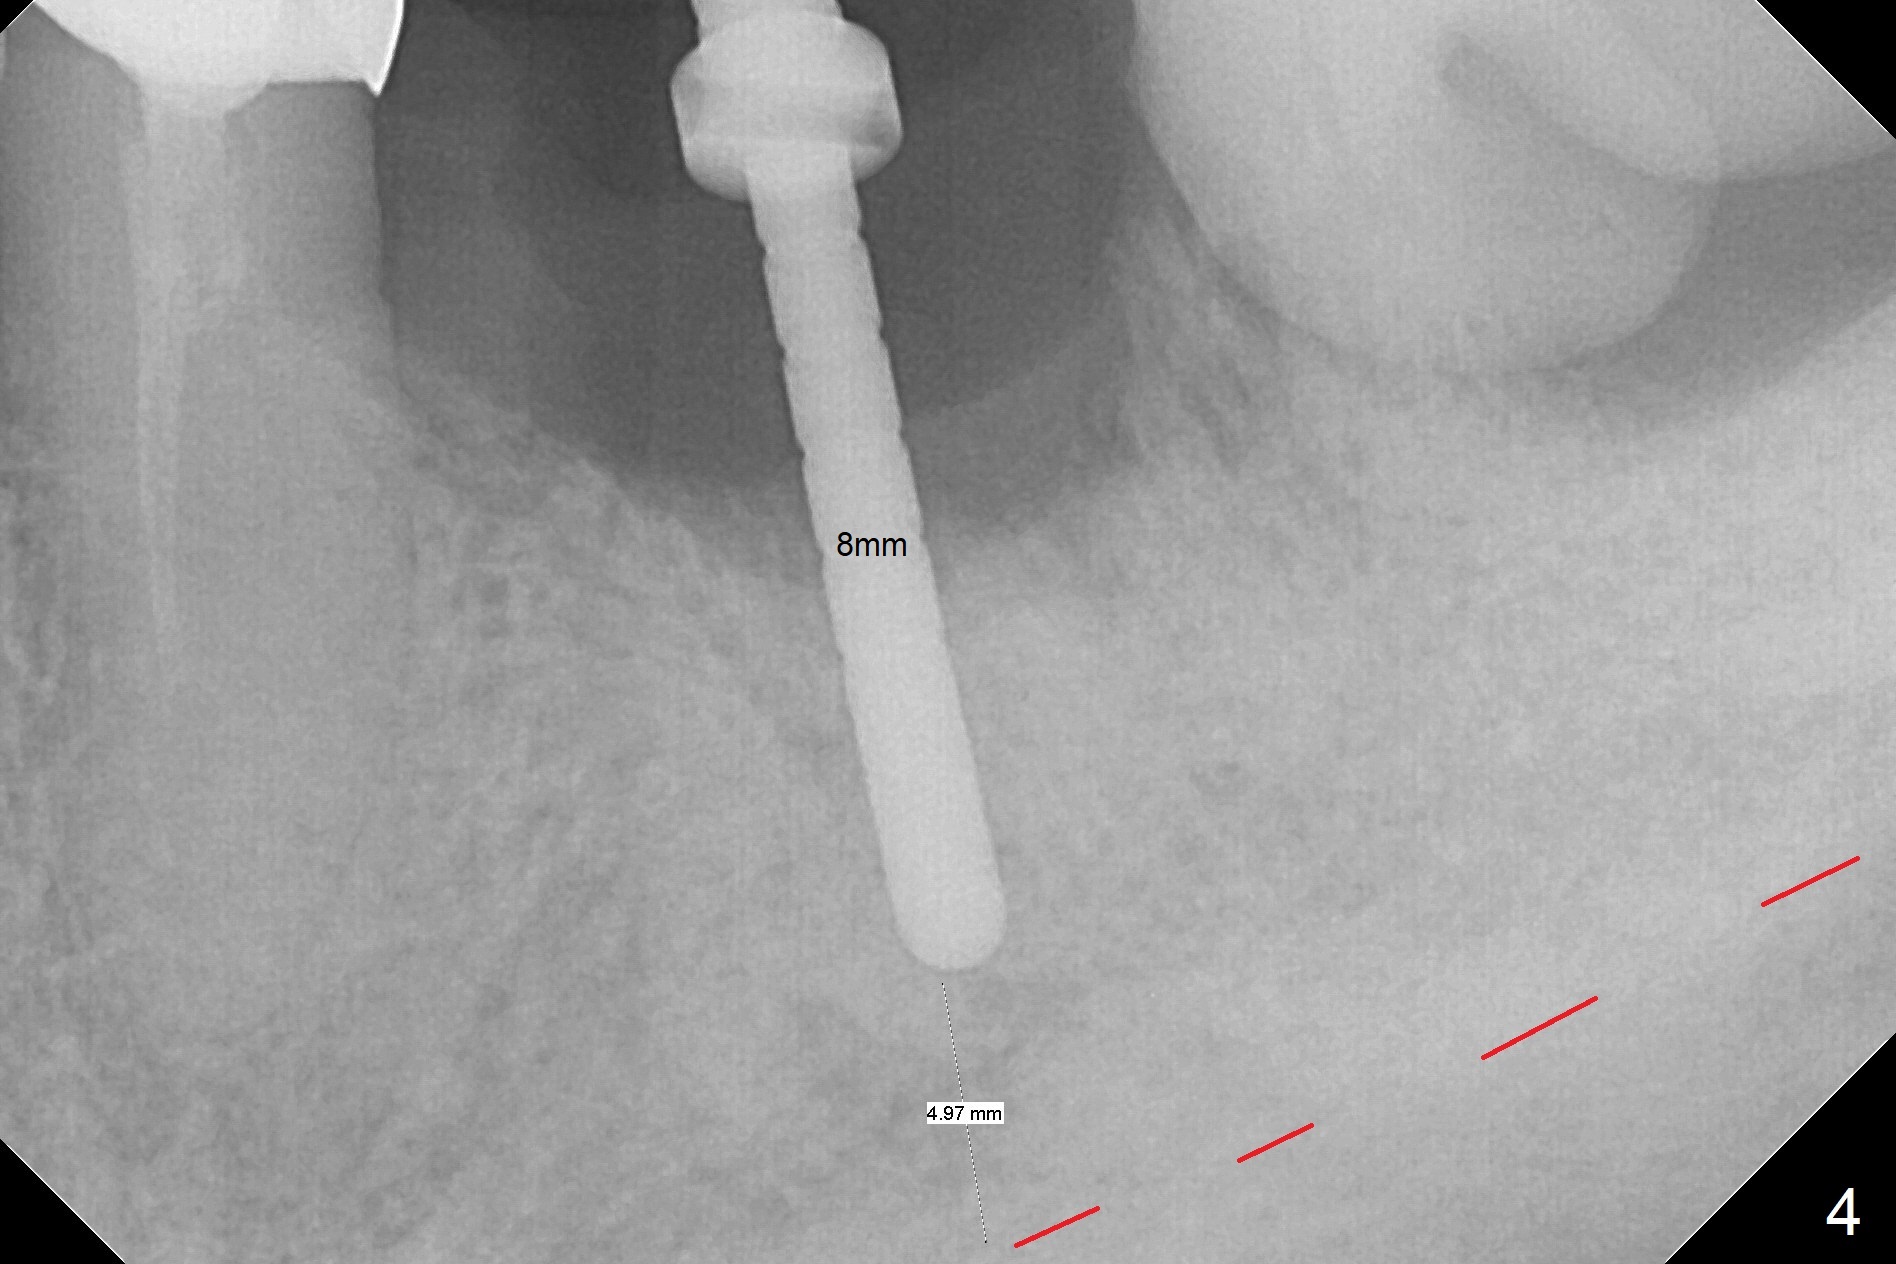

After extraction of the supraerupted tooth #19 with severe buccal gingival recession, the buccal and lingual plate are found to be lost. The sockets are fused and flat without the septum. The bone is hard and painful for the initial osteotomy with infiltration anesthesia (Fig.2). Following block anesthesia, the initial osteotomy depth extends to 8 mm (Fig.3,4). With apparent 4.9 mm clearance, the osteotomy is further extended to 10 mm. The osteotomy walls are apparently intact without severe hemorrhage after each drill. Due to the thick gingiva and severe bone loss, a 5x12 mm implant is intentionally placed 3 mm above the base of the socket bone (Fig.5,6 (yellow dashed line)). Vanilla Cortical and Cancellous allograft (Fig.6 *) is placed around the exposed implant and 7.8x5(6) mm abutment with 4 and 2 mm buccal and lingual gaps. Next collagen plug cut in strip is placed to fill the most coronal aspect of the socket (Fig.7 *). The buccal and lingual gingivae are approximated with sutures proximally. Finally periodontal dressing is applied. Since the Inferior Alveolar Canal is vague in intraop PAs (Fig.4,5), there is worry about potential nerve damage during and after osteotomy. This should be no issue if preop panoramic X-ray is reviewed with measurement (Fig.8). The bone graft appears to remain in place nearly 4 months postop (Fig.9). Two weeks later, he returns for impression. When the provisional is removed, the gingiva is unhealthy. Without the provisional and with improved oral hygiene, the gingiva is healthy one week later, but the tooth #18 is symptomatic. The latter is extracted with socket preservation (Fig.10 *). There is no apparent bone loss around the implant at #19 6.5 months post cementation (Fig.11).